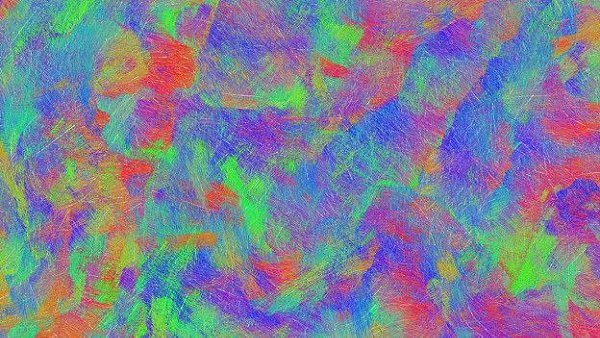

фото 2 - Мозг новорожденного представляет собой густую сеть нейронных связей, картографирование которых – основная задача проекта "Развитие коннектома человека"